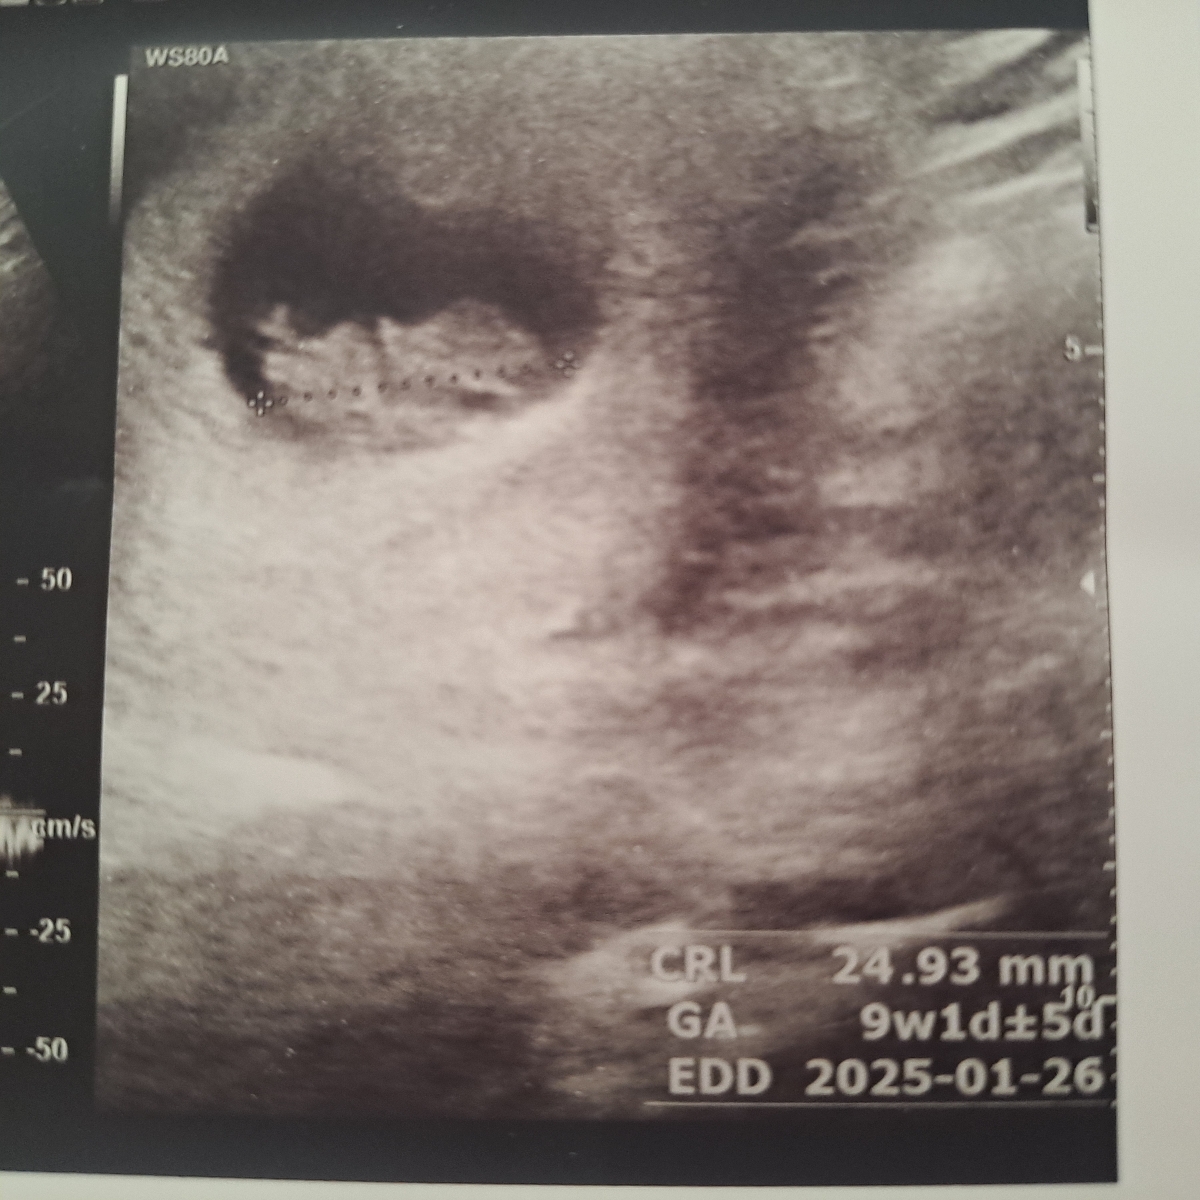

سونوتوبفرست حدس بزنم

جدی الان میفرستم

عکس جنین

مشخص نیس

فقط سرش

بفرست

سرش جوریه که ۴گوشه داره

دختره نی نی

از فرم جمجه اش کپی عکس ان تی دخترمه

اینم برا انتی

اینم ان تی